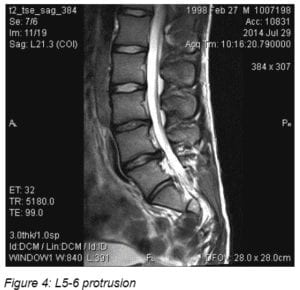

Magnetic Resonance Imaging (MRI) Imaging was available at the January visit and demonstrated prominent protrusions at two levels. See Figures 2 to 4

The physical therapists and pain physician helped the parents identify an appropriate pediatric surgeon at a well-known medical center in a large metropolitan area. A consult was obtained within 2 weeks. The surgeon requested a 6-week trial of 15 mg. oral Meloxicam. This brought no change in symptoms and laminotomy and microdiscectomy on left L5-L6 and right L6-S1 surgery was performed in March 2015.